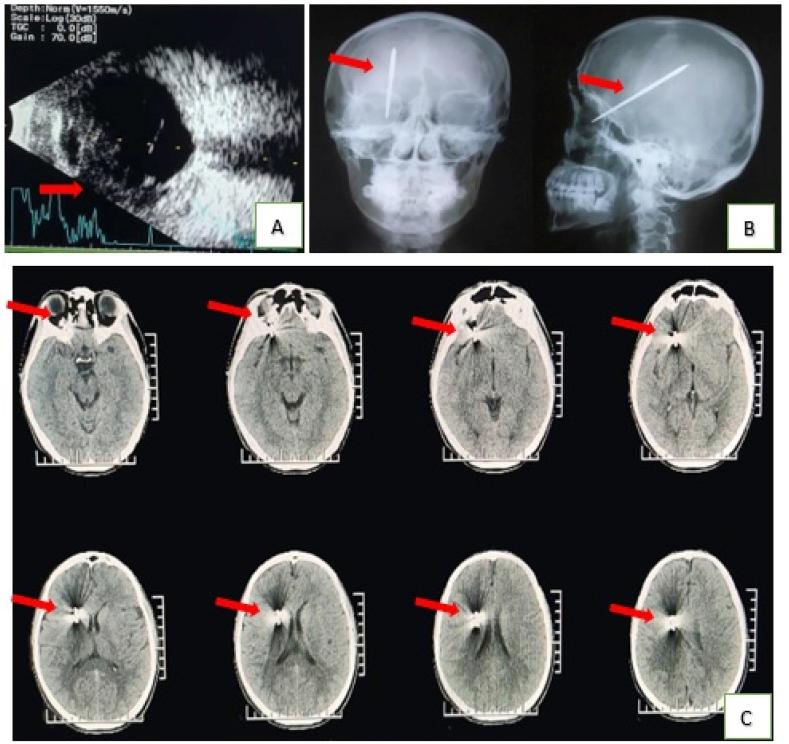

Transorbital-penetrating intracranial injury due to a homemade metal arrow: A case report.

A transorbital-penetrating intracranial injury (TOPI) is an unusual traumatic brain injury. This rare injury has the potential to result in serious and fatal brain damage with a high mortality rate and requires prompt multidisciplinary surgical intervention. Here, we describe an interesting case in which a patient who presented with accidental penetrating injuries of the brain was found to have a transorbital-penetrating intracranial injury (TOPI). We chose an anterior approach to the foreign body above the entrance wound for removal in a retrograde manner with fluoroscopic guidance. The patient remained well with no complications and was discharged on postoperative day 10. Reasonable diagnostic imaging, surgical planning, and careful post-surgery management can increase patients successful outcomes.